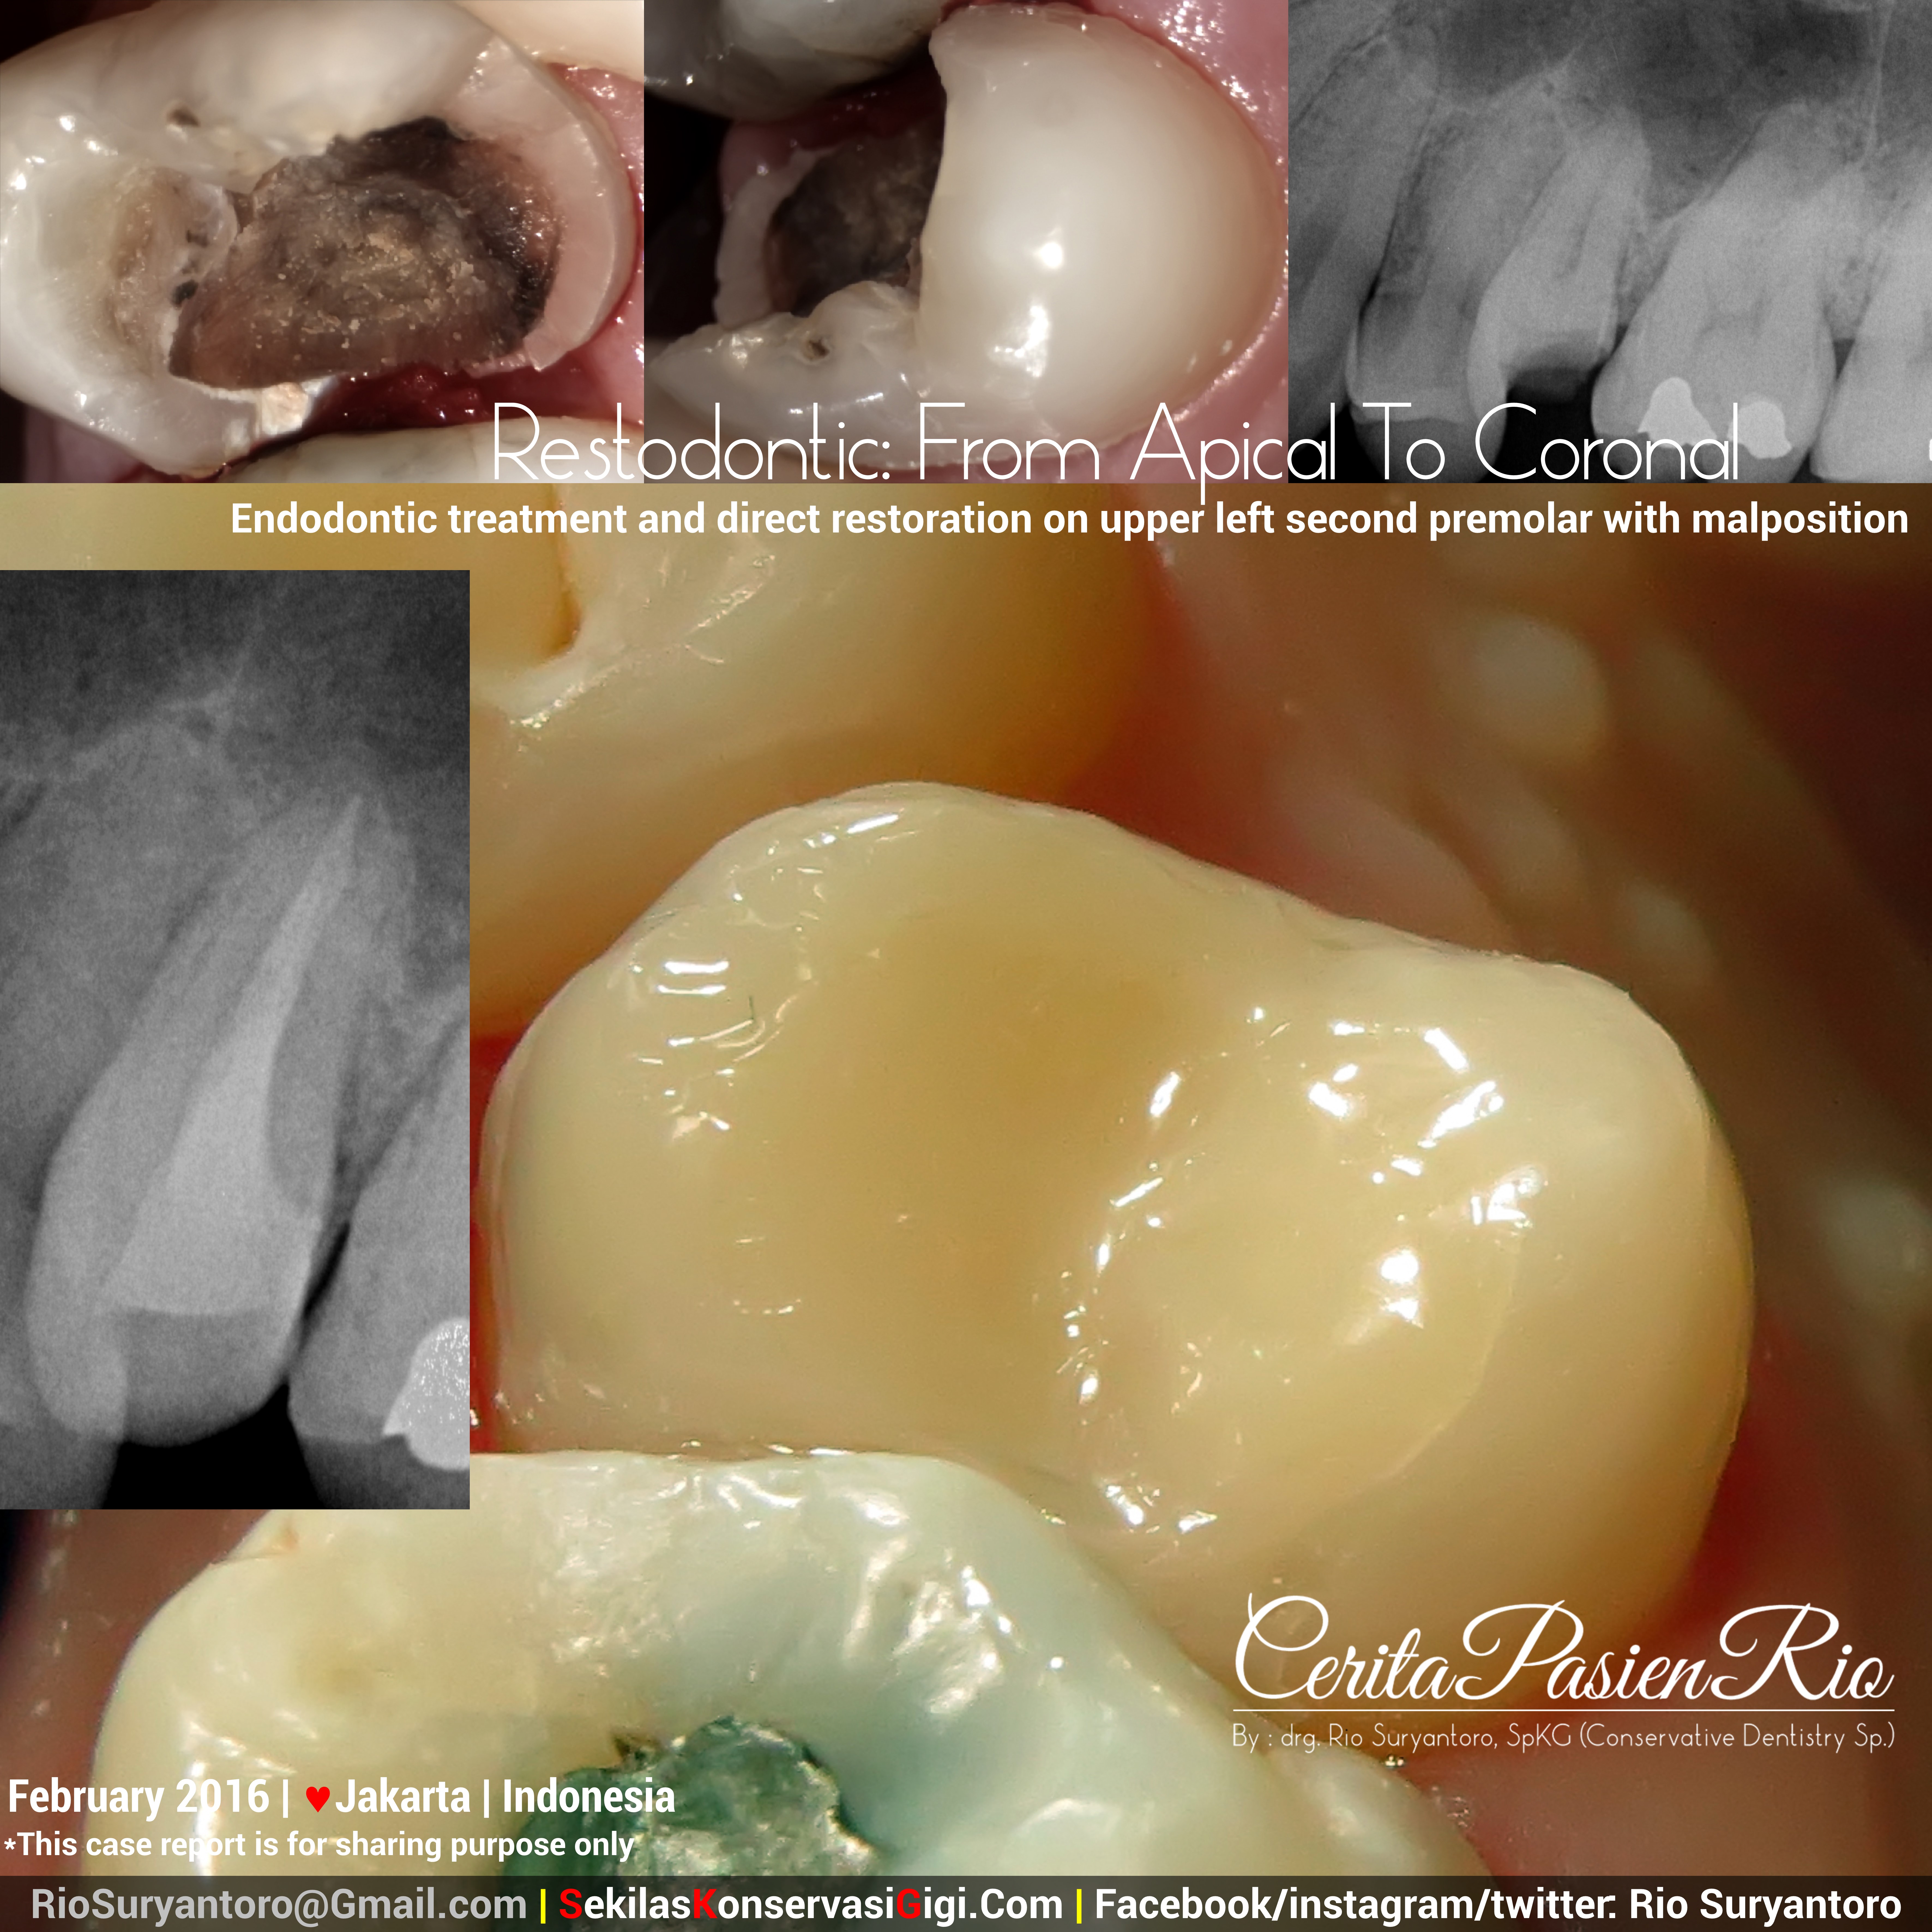

drg. Rio SpKG restodontic endodontic